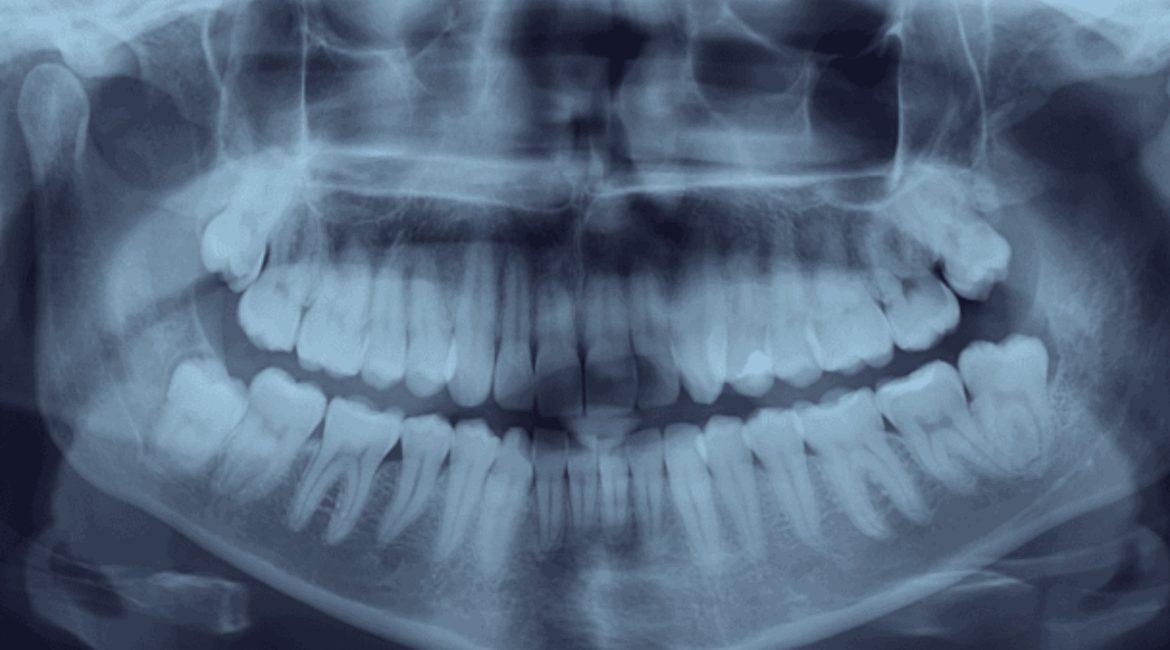

Як діагностується ретенція зубів?

Сучасна стоматологія використовує кілька високотехнологічних методів діагностики для виявлення ретенованих зубів. Ортопантомограма, або панорамний знімок, дозволяє отримати повну картину розташування зубів у щелепі та виявити порушення їх прорізування. Для оцінки прикусу часто застосовується телерентгенограма — цей метод допомагає лікарю визначити положення щелеп та взаємозв’язок між зубами.

Найточнішим методом є конусно-променева комп’ютерна томографія (КПКТ), яка дозволяє з високою точністю визначити положення ретенованого зуба, оцінити його близькість до важливих анатомічних структур і виявити можливі ризики, зокрема пошкодження коренів сусідніх зубів.